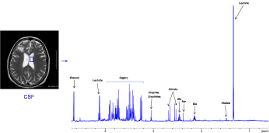

Magnetic Resonance

High Resolution Liquid NMR

High Resolution Liquid NMR High Resolution Magic Angle Spinning (HR-MAS) NMR

High Resolution Magic Angle Spinning (HR-MAS) NMR Time Domain NMR (TD-NMR)

Time Domain NMR (TD-NMR)